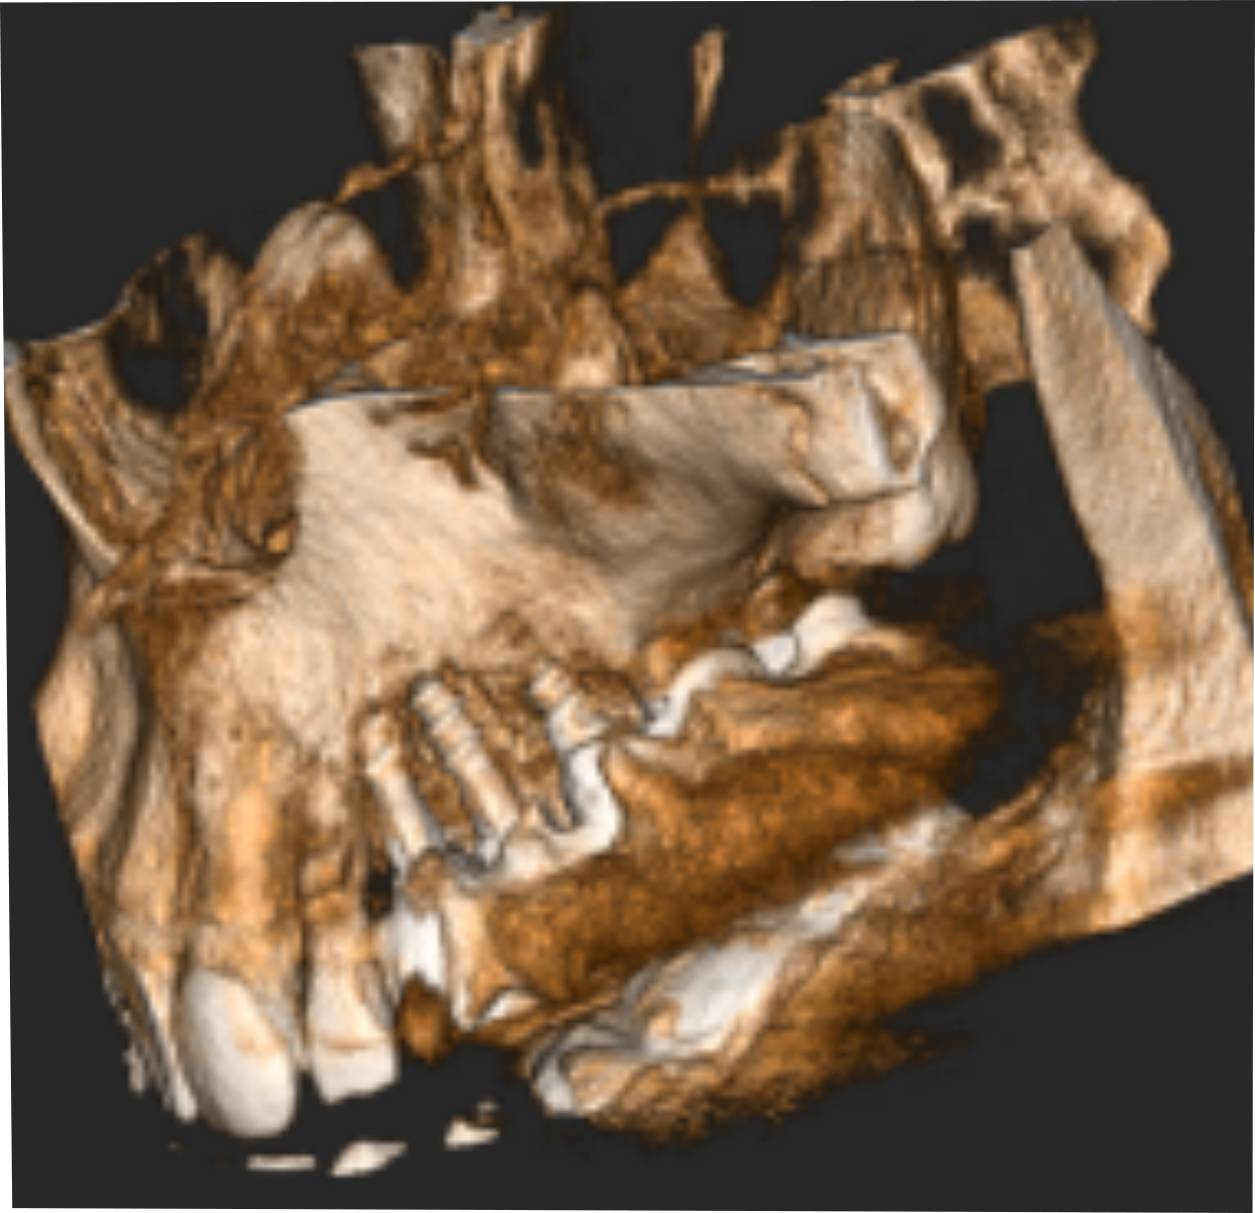

Gracias a la adquisición de alta resolución de nuestro equipo CBCT NewTom 5G XL, y con las últimas innovaciones en impresoras 3D, ofrecemos la posibilidad de reproducir una muestra tridimensional exacta de la zona anatómica estudiada.

Si lo enfocamos en la vertiente dentaria, se nos abre un abanico de posibilidades en el campo de la implantología, siendo de gran utilidad para la planificación in situ de la técnica quirúrgica y de los materiales que se utilizarán para dicha intervención.

Podemos reproducir desde una arcada completa hasta un único diente, a escala 1:1 para poder trabajar sobre la muestra como si lo estuviéramos haciendo directamente en el paciente adelantándonos así a la cirugía.